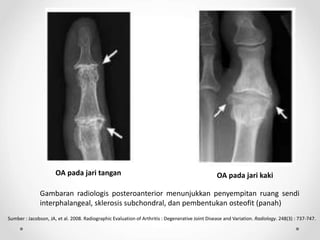

OA pada jari tangan OA pada jari kaki

Gambaran radiologis posteroanterior menunjukkan penyempitan ruang sendi

interphalangeal, sklerosis subchondral, dan pembentukan osteofit (panah)

Sumber : Jacobson, JA, et al. 2008. Radiographic Evaluation of Arthritis : Degenerative Joint Disease and Variation. Radiology. 248(3) : 737-747.